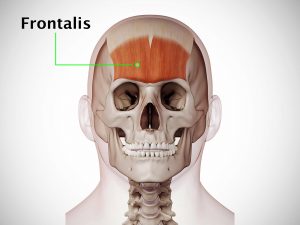

Whereas acute stress resulting from trauma may temporarily block pain, chronic physical or emotional stress can cause pain and lowering your tolerance to pain, stress makes existing discomfort worse. For example, if you are worried that pain results from a serious disease, it may be hard to bear, but once you know that this is not the case, you may find the pain much more tolerable. Long-term stress also causes physical tension, which makes you prone to headaches and minor injuries, such as strained muscles.